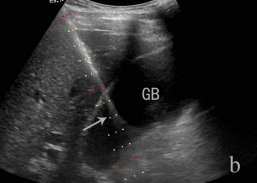

胆管穿刺置管-                                                                                                                         a超声引导胆管穿刺置管引流              b 超声引导胆囊穿刺置管引流                 c超声引导肾盂穿刺置管引流